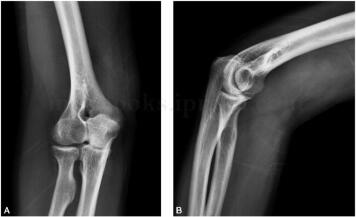

男,56岁,患者1年前无明显诱因发现右肘部肿物,较小,逐渐增大,右肘关节尺侧肿胀,无皮肤发红发热,可活动,无压痛,尺神经Tinel征阴性。右肘关节活动正常,上肢皮肤感觉正常(图1~3)。

图1 X线:右肱骨下段软组织局限性密度增高,骨质未见明显破坏征象